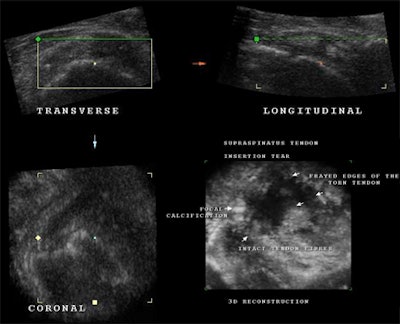

![]() |

| Multiplanar imaging, including 3D reconstruction, of a torn supraspinatus tendon with underlying tendinitis (with no history of trauma). Lower right, note the focal calcification at the insertion of the tendon into the greater tuberosity and smaller calcifications throughout the tendon. The intact portion of the remaining tendon is demonstrated beside the anechoic fluid-filled space where the tendon has broken. The free, frayed edges of the tendon are clearly visible. |